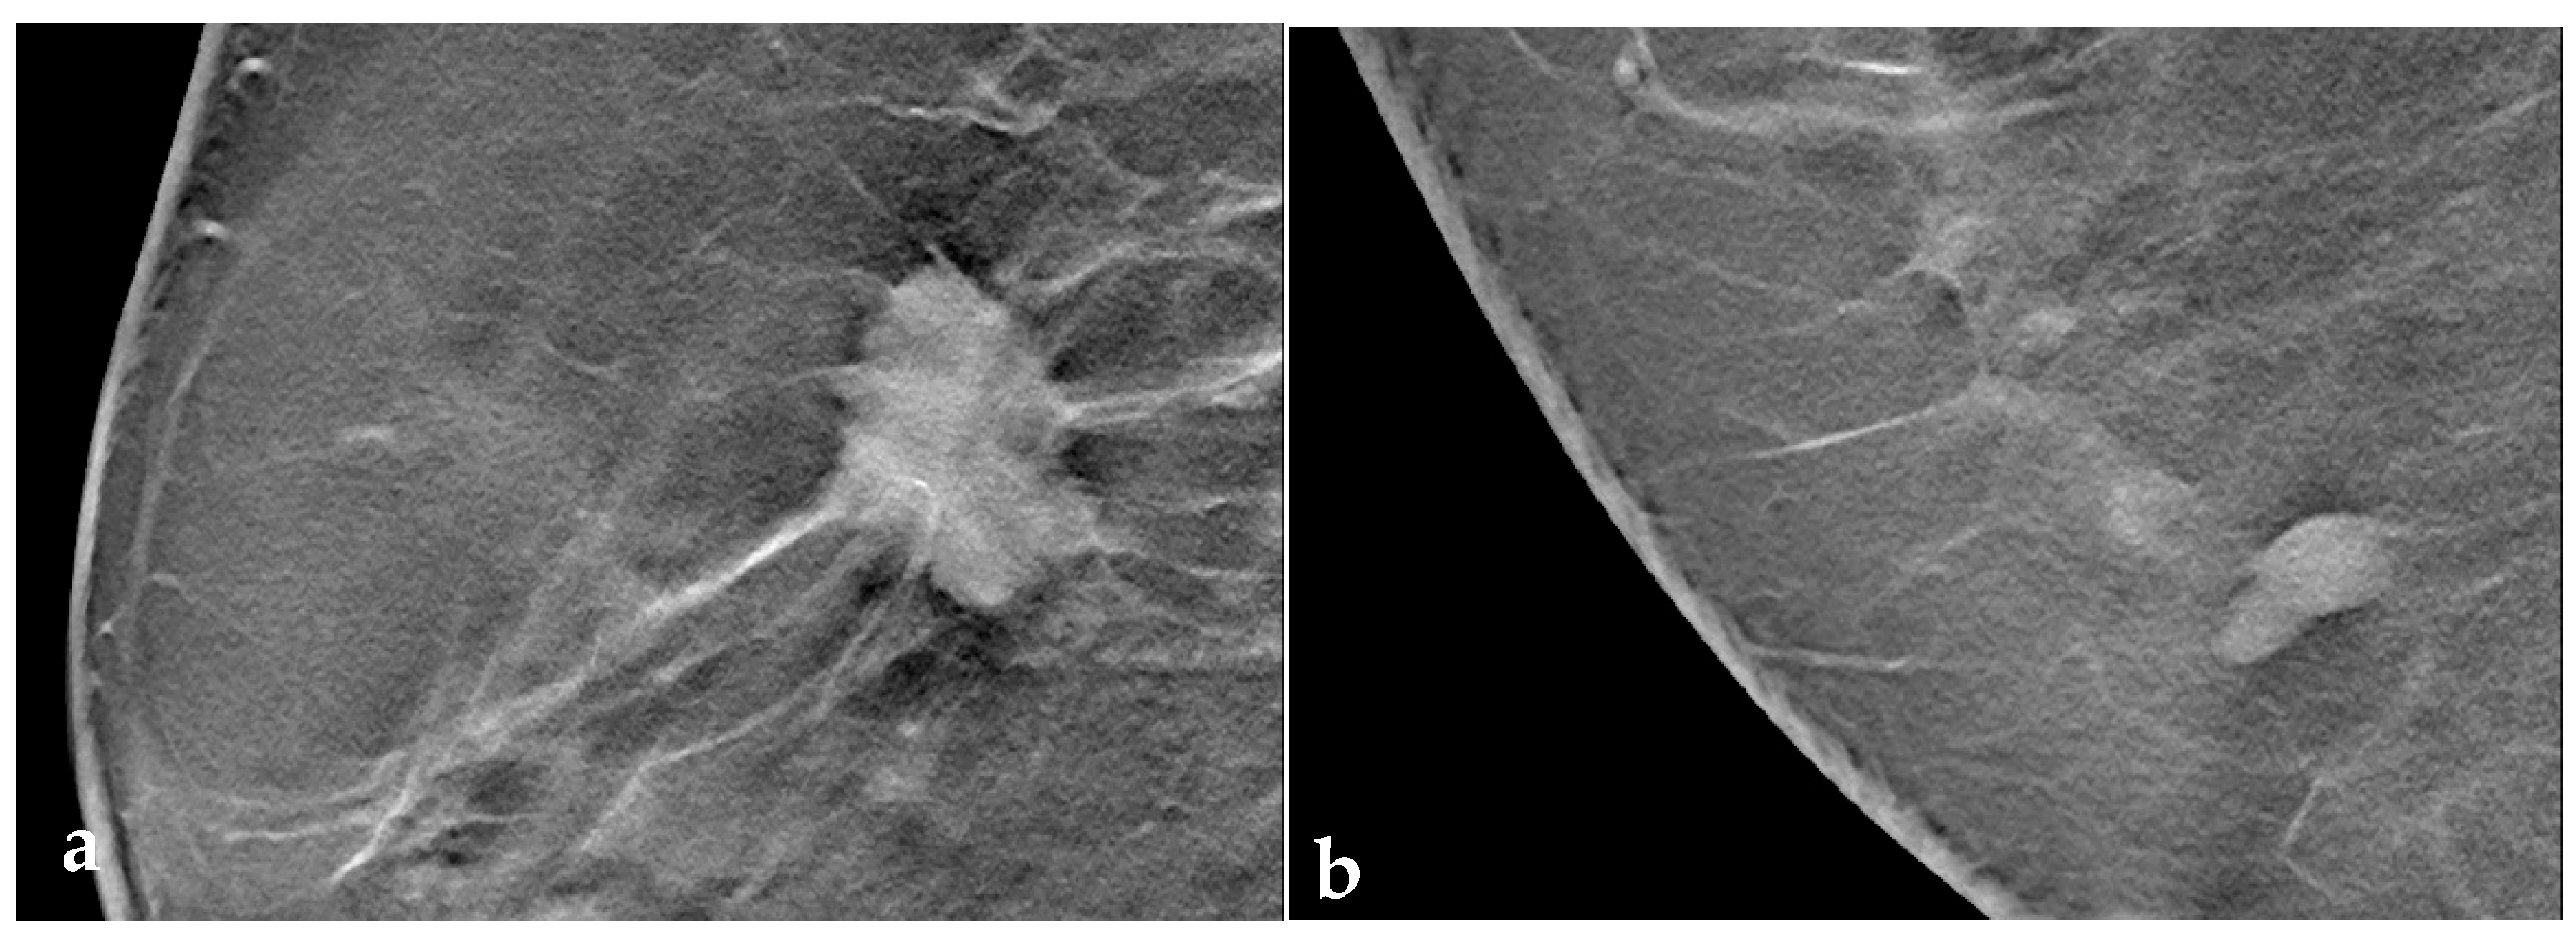

3.3. Tomosynthesis Evaluation